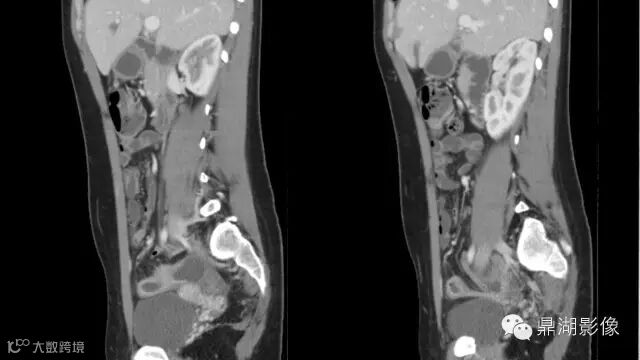

what's the meaning of fat halo sign?

粘膜下水肿或脂肪沉积,可致肠壁内呈低密度层(halo征),其最初用来描述溃疡性结肠炎,是良性肠道病变的结果,无特异性,也可存在于放射性肠炎,移植-受体疾病和慢性缺血性肠炎以及单性的肥胖症患者。

Fat halo aslo can be seen in normal terminal ileum.

It is the comb sign the most specific sign for crohn's disease.